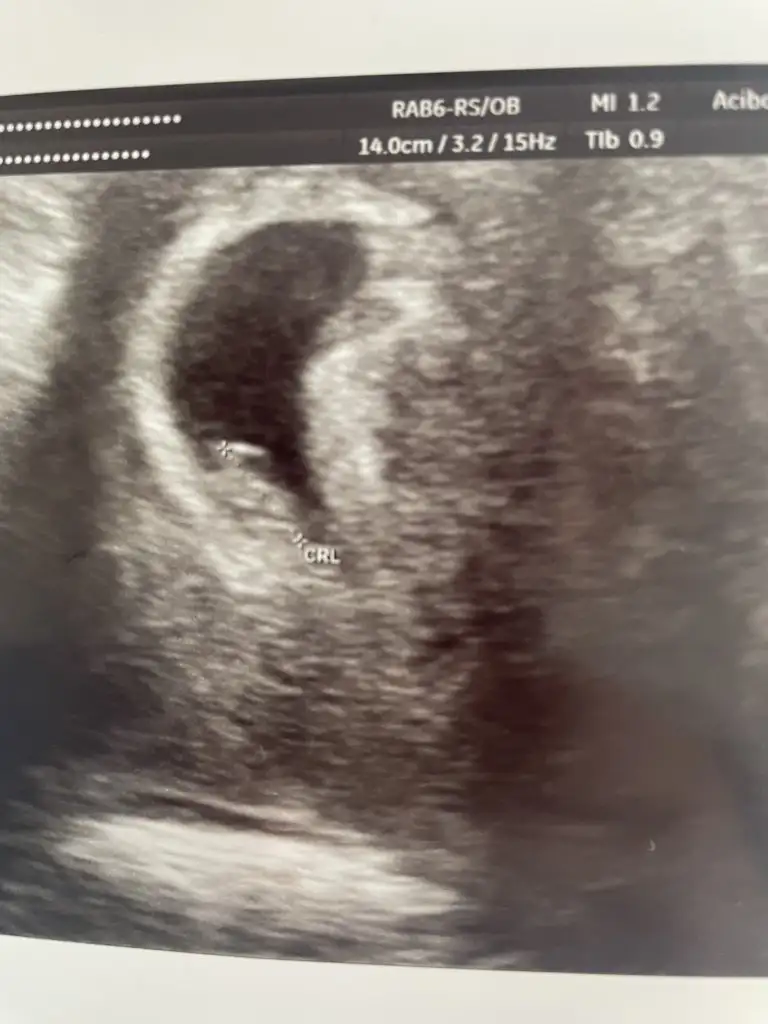

Bizede bak canan teyzesi 🙈😂6+5 ilk götüntümüzdü bu

Eklentiler

• FD31CEB3-673E-44F0-AC11-07CB1D013CF8.webp

FD31CEB3-673E-44F0-AC11-07CB1D013CF8.webp

32,1 KB · Görüntüleme: 47